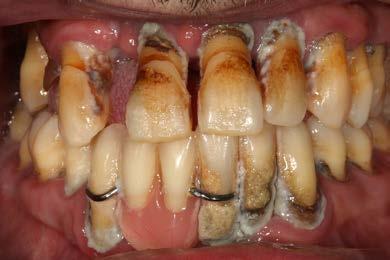

En las imágenes tomadas en la primera visita podemos ver la gran pérdida de

2. Situación inicial

paciente.

inserción de los dientes, el mal control de la placa bacteriana por parte del paciente y la prótesis inferior desadaptada.

Figura 7 Cone-beam de control de la zona más distal del primer cuadrante donde se planifica un implante extracorto

Presentamos el caso de un paciente de 35 años, fumador, con enfermedad periodontal agresiva en fase avanzada y un deficiente control de la higiene oral. El paciente acude a nuestro centro solicitando un tratamiento restaurador con implantes dentales, tras haber experimentado varios fracasos con prótesis removibles previas. Durante la exploración intraoral, se observa periodontitis avanzada, con una significativa pérdida de inserción en la mayoría de los dientes, un control inadecuado de la placa bacteriana, y una prótesis removible mal ajustada anclada a dientes con movilidad (Figura 1 y 2). En la radiografía panorámica inicial podemos constatar la gran pérdida ósea horizontal, en todas las piezas dentales, con algunas de ellas ancladas únicamente en el tejido gingival. Además vemos también en la imagen

cómo existen varias piezas dentales con pronóstico dudoso con grandes caries con afectación radicular que deben ser extraídas, como los molares de los sectores posteriores maxilares, tanto derecho como izquierdo (Figura 3).